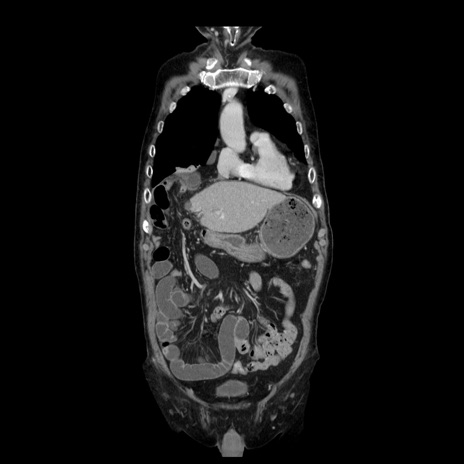

症例21(冠状断像)

【症例】70歳代男性

【主訴】腹痛

【現病歴】肝硬変・肝細胞癌にてかかりつけの方。約9時間前に食後より腹痛出現。症状が徐々に増悪し、嘔吐出現したため来院。

【既往歴】肝硬変、肝細胞癌(RFA、TACE後)

【身体所見】意識清明、表情苦悶様、BT 36℃、BP 129/78mmHg、P 88bpm、SpO2 97%(RA)、右上腹部から心窩部にかけて圧痛あり、反跳痛なし、筋性防御あり。

【データ】WBC 5800、CRP 0.16